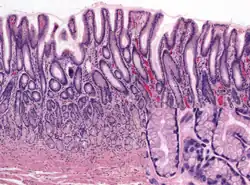

Het maagslijmvlies (antrale mucosa), H&E-gekleurd. Bovenaan de coupe zijn geplooide, secretoire cellen zichtbaar. -

Een van de meest populaire kleuringen is hematoxyline en eosine (H&E), de routinekleuring in histologische en pathologische laboratoria. De basische kleurstof hematoxyline kleurt zure delen van de cellen donkerblauw (zoals de kernen die immers rijk zijn aan nucleïnezuren). Eosine is een zure kleurstof, die zich juist hecht aan eiwitrijke componenten van het cytoplasma, zoals collageen, spiervezels en rode bloedcellen. Bij deze combinatie worden vrijwel alle structuren aangekleurd en krijgt men een zeer volledig beeld van het weefselmateriaal.[8]